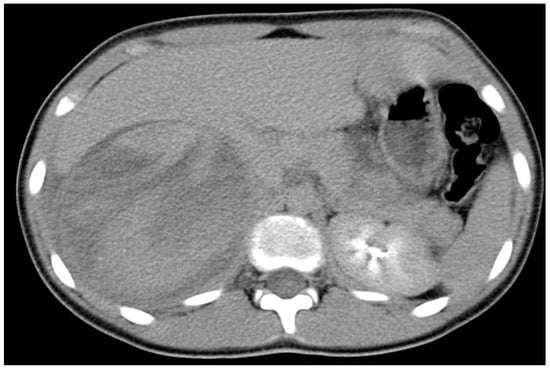

4. Spleen Injury

5. Liver Injury